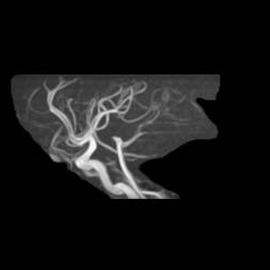

頭部MRA:脳動脈瘤の有無、血管の太さなど、脳の血管の状態を確認します

通常の頭部MRI検査では、一度にMRIとMRAの検査を行っています